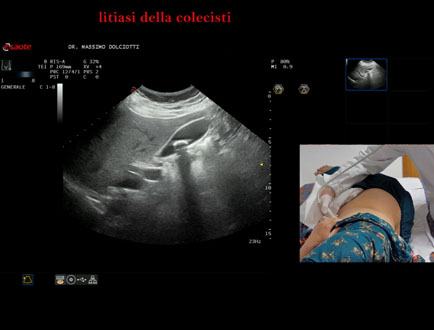

Data inserimento: 13/10/2025

Ecografia del: 07/10/2025

Strumento: Esaote MyLab Eight

Sonda: Convex Multifrequenza 1-8 MHz

Età Paziente: F 49 anni

Motivazione dell'esame: follow up per litiasi della colecisti dopo trattamento con acido ursodesossicolico.

Commento all'esame: le immagini ed il video documentano nel lume della colecisti, immagine iperecogena, delle dimensioni di 16,1 mm, con cono d'ombra posteriore, mobile al decubito, da ricondurre a litiasi.

Conclusioni: litiasi della colecisti (gallstone).

Presentazione: Dr. Massimo Dolciotti - Ancona

Elaborazione digitale: Andrea Dini - Ancona